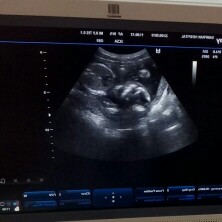

21วีค กำหนดคลอด 3ม.ค.63 ลูกชายค้า

น้องหันหน้ามาเหมือนกันคะ

ใช่คะ น้องหันหน้ามา

เต็มๆหน้าไปเลย